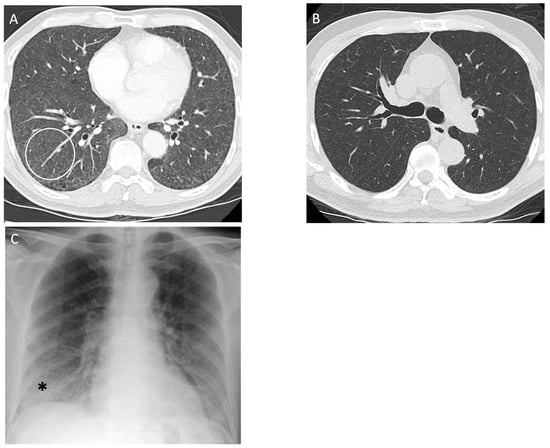

Exposure to metals such as tungsten and rarely aluminum have also been reported to produce isolated desquamative interstitial pneumonia (Figure 6) [57]. On CT, desquamative interstitial pneumonia manifests as a lower lung zone predominance of consolidation and ground glass opacities with the formation of cystic air spaces. This inflammation can lead to fibrosis with traction bronchiectasis [58]. Cystic air spaces and adjacent traction bronchiectasis may persist even after the inflammation resolves.

Figure 6.

A 56-year-old male with a history of grinding aluminum for 5 years diagnosed with desquamative interstitial pneumonia (DIP) on surgical lung biopsy. There was a 10 pack year smoking history, but it was remote to the presentation, and the DIP was attributed to occupational exposure. (A) Axial computed tomography of the upper lung zone reveals emphysema (white circle), and the (B) basal lung zone demonstrates extensive ground glass opacity (arrows) with subtle small cysts or lucencies on close inspection; (C) posteroanterior and (D) lateral view chest radiographs 6 months later show persistent basilar opacities (black arrow).